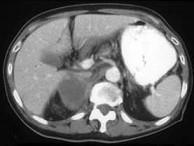

问题 男,75岁,右侧胸痛伴咯血3月余,胸部CT提示右侧中央型肺癌,请结合图像,作出诊断 ( )

选项 A、右侧肾上腺癌 B、右侧肾上腺嗜铬细胞瘤 C、右侧肾上腺转移瘤 D、右侧肾上腺腺瘤 E、右侧肾上腺囊肿

答案 C